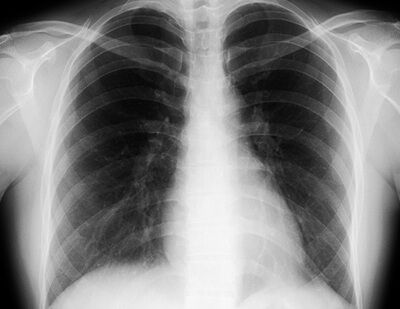

【画像】レントゲンを撮ったケニアの患者さん、肺にとんでもない影が見つかる